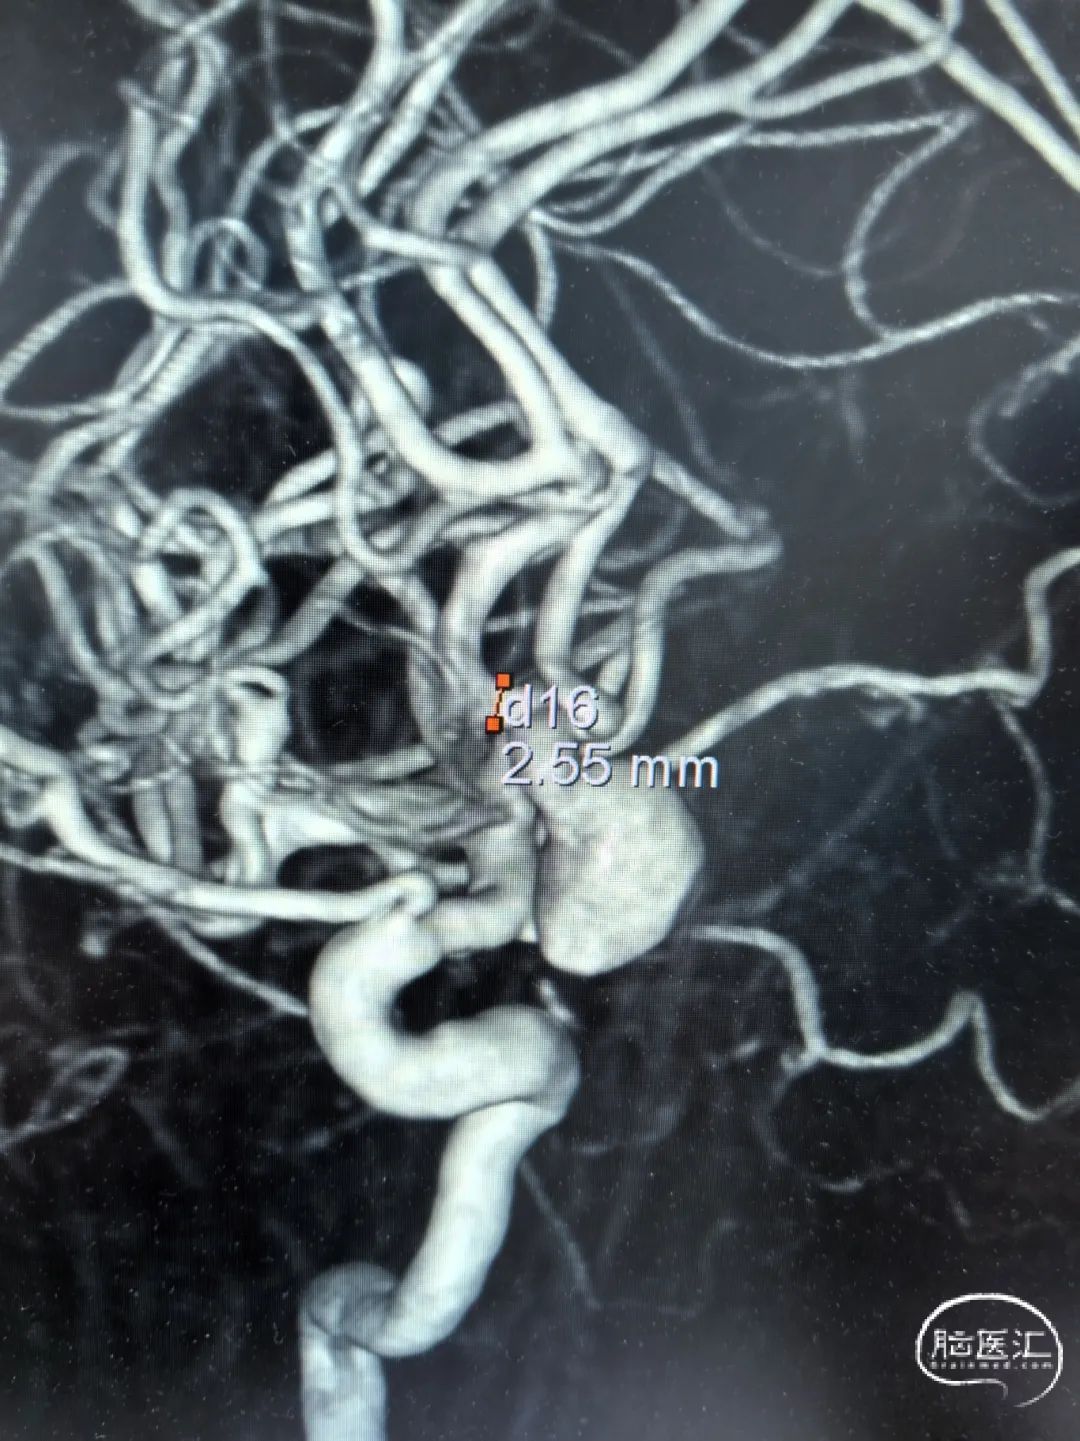

2025-1-19 DSA造影3D重建及方案讨论:

DSA造影3D重建测量

拟行脑动脉瘤密网支架置入术。

2.5mm*15mm Surpass Evolve密网支架,支架锚定区为右侧A2~A1